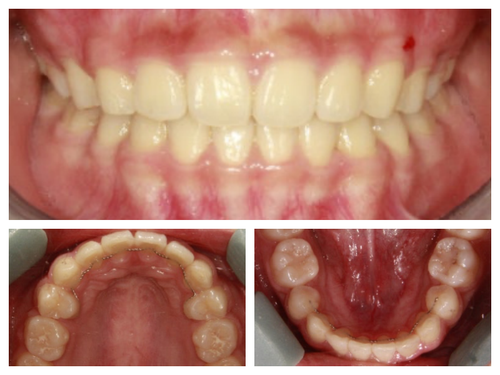

사실 골격적인 비대칭이 심해서 교정이 끝나도 비대칭이 남겠지만 돌출이 개선되면 훨씬 예뻐질것이기에 과감히 발치를 하고 좌,우 최대한 중심선을 맞추면서 교정을 끝낸 케이스

입이 들어가서 예뻐진 것 뿐아니라 사진을 찍으면 두드러지던 비대칭도 많이 줄어들었다.

네 개의 소구치를 발치하고 교정을 시작했다.

돌출입 교정을 통해 입술의 모습이 많이 바뀌니 잇몸 노출량도 훨씬 줄어서 웃을때 신경이 더 쓰인다고...